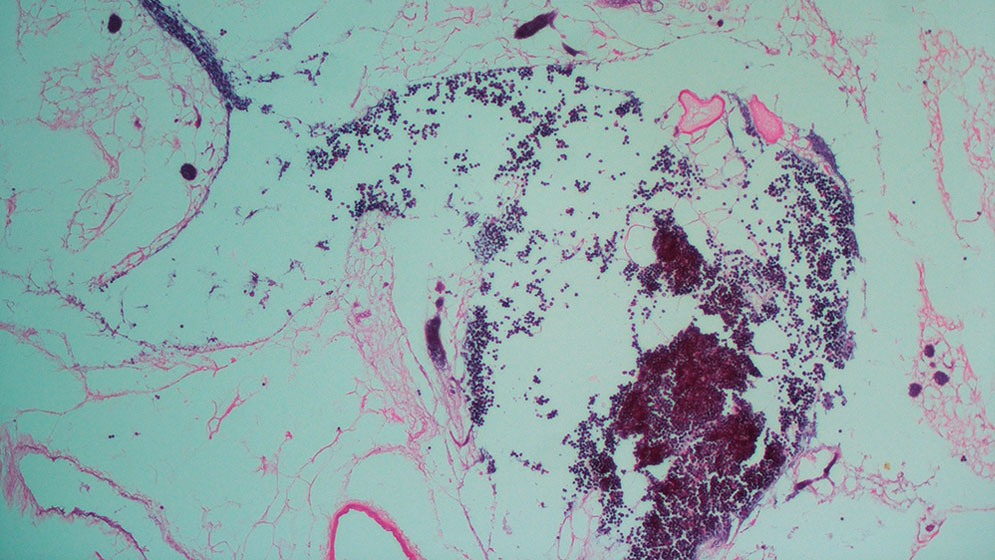

“Tras la cirugía se observó la correcta perfusión del órgano y la producción de orina. A través del microscopio se pudo observar la recelularización del órgano por parte de las células endoteliales humanas, que previamente habían sido marcadas con una proteína verde fluorescente (GFP, por sus siglas en inglés)”, explica Geraldine Haeublein, becaria doctoral del CONICET y primera autora del estudio.